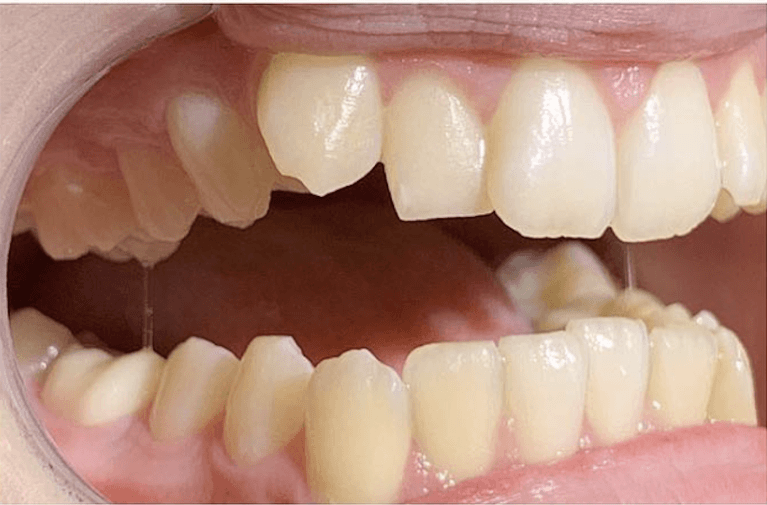

Before and after with Invisalign orthodontic treatment. Pictures taken with different phones at different setting. Used total of 27 aligners/trays. Treatment time 13.5 months